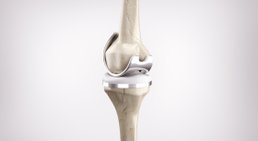

Knieprothese

Eine Knieprothese ersetzt ein verschlissenes Kniegelenk - die Aufgabe der Prothese ist es, die Form und Funktion des menschlichen Kniegelenks nachzuahmen.

Knie: Kniearthrose, Kreuzband- und Meniskusriss, Entzündungen, chronische Reizungen, Patellasyndrom, Gelenkfehlstellungen, Knorpelschäden, Bursitis trochanterica; Operationen: Knorpelchirurgie, Kniearthroskopie, Osteotomie, Versorgung mit Prothesen